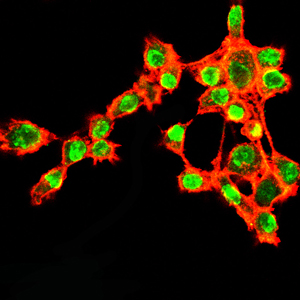

分类: 科研抗体货号: 20335别名: K5; DDD; EBS2; KRT5A; KRT5应用: IHC,IF反应种属: Human